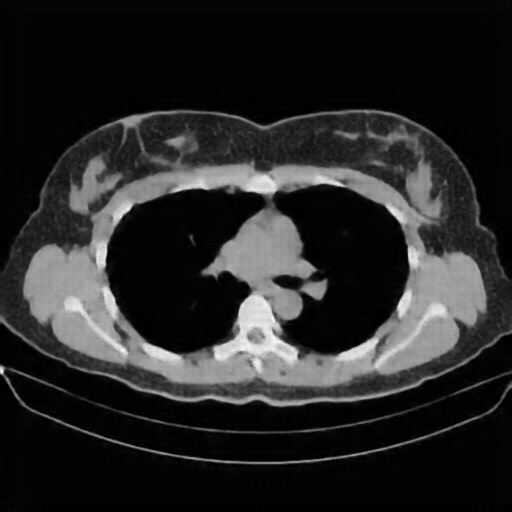

Image Grid

4Γ—3 grid: Rows show different image types (Original NATIVE, Reconstructed NATIVE, Original VENOUS, Generated VENOUS), Columns show windowing techniques (No Window, Lung Window, Mediastinum Window)

Reconstructed NATIVE CT scan (cycle consistency)

Full window (WL 1023.5, WW 4095 β†’ Low βˆ’1024, High +3071)

Lung window (WL -600, WW 1500 β†’ Low βˆ’1350, High +150)